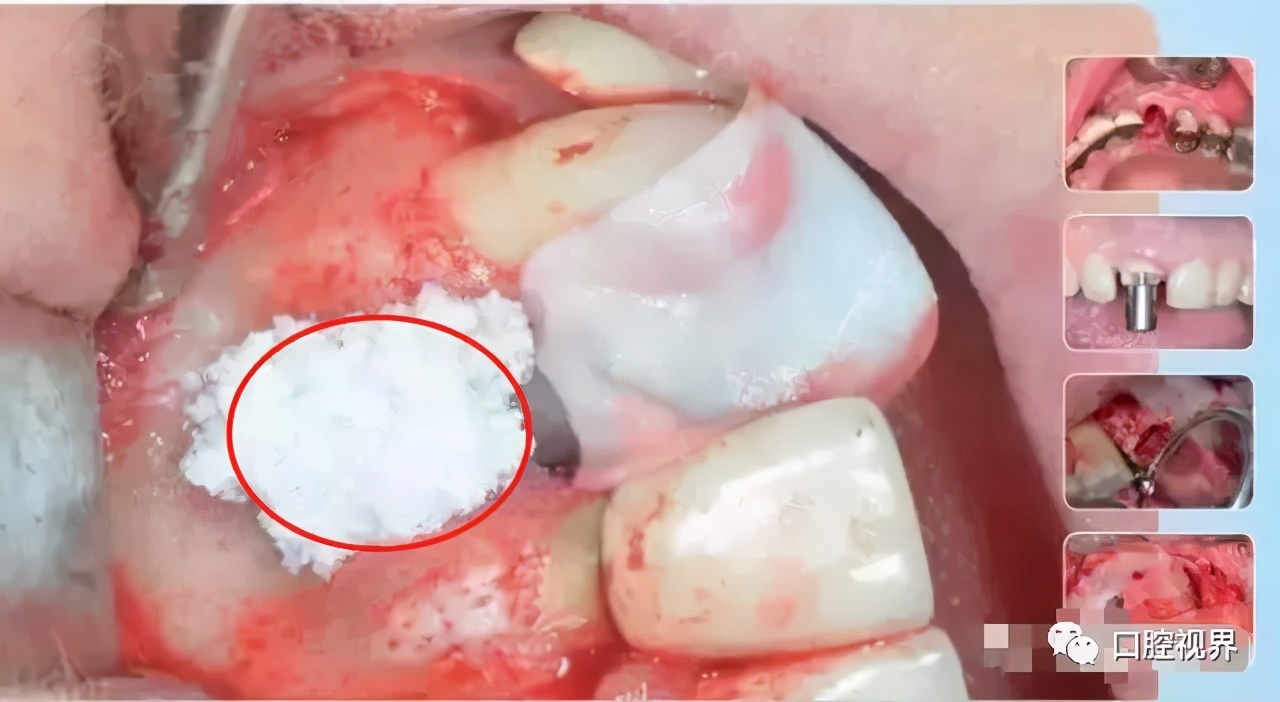

就是将口腔专用的骨粉骨粒植入牙创口,在面上再覆盖一层可吸收膜,从而达到修复牙槽骨的作用。

临床研究表明,拔牙术后牙槽骨可能会因此减少,有些骨板过薄的甚至会被完全吸收,而位点保存正是为此而存在的。

这足以以假乱真的修复方式,不仅是为了保存牙槽骨,更是为后期种植牙做好前提条件。

这种情况下是可以考虑进行位点保存手术的。如图——